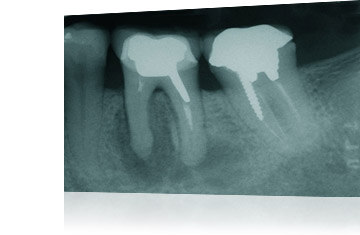

L'endodonzia è quella parte dell'odontoiatria che si occupa di tutte le patologie della polpa (il "nervo" dei denti) e degli effetti che tali problematiche possono causare al dente stesso e ai tessuti circostanti.

L'importanza di ricevere corrette e tempestive cure endodonziali è cruciale: un bravo endodonzista, o comunque un odontoiatra dotato di un'ottima preparazione in endodonzia e di strumenti diagnostici all'altezza è in grado di fare la differenza tra un dente ben trattato ed un dente irrimediabilmente perso.

Lo Studio Fratus garantisce ai suoi pazienti un aggiornamento continuo e una diagnostica immediata ed efficace attraverso macchinari per radiografie panoramiche disponibili internamente.